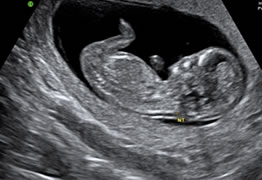

Radyologlarımız tarafından ultrasonografi çekimlerinde tüm batın, üriner sistem, meme, yumuşak doku, tiroid ultrasonografisi , obstetrik ve folikülometrik ultrasonografi uygulamaları yapılmaktadır.